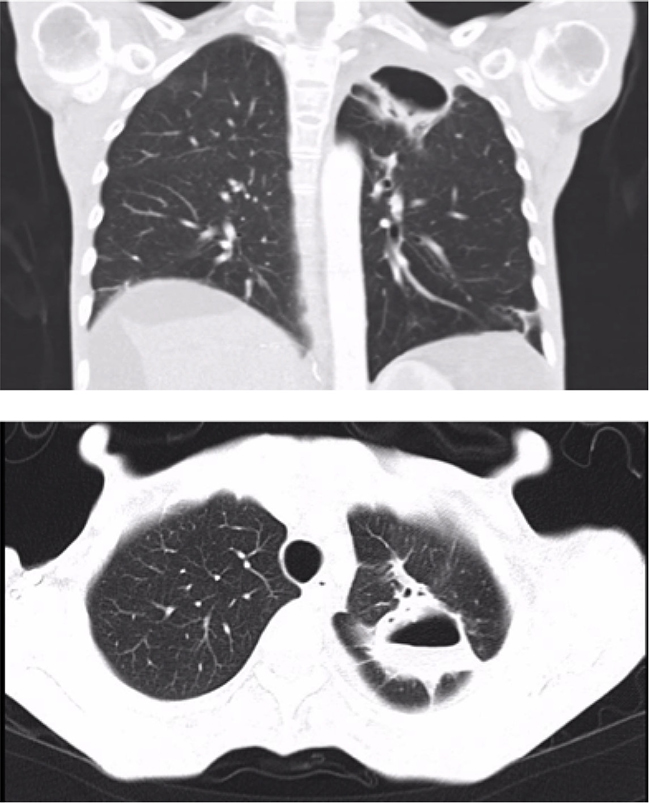

A bronchoscopy was performed with no macroscopic findings. No malignant cells were observed on cytology of a bronchioalveolar lavage (BAL) and microbiologic cultures were negative. Sorafenib was discontinued after 4 months of treatment. Repeated CT scans performed one and three month after discontinuing Sorafenib showed a reduction in the size of the pneumatocele (Figure 2). Sorafenib was not reintroduced and the patient died 4 years after the pneumatocele was diagnosed due to tumor progression.

Figure 2: Lung cavity improvement after discontinuing Sorafenib treatment (27 × 28 × 42 mm) (Case 1).